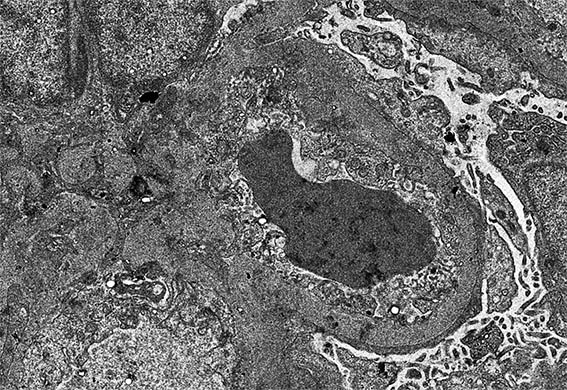

Figure 12. EM, original magnification, X2,100.

Figure 12. EM, original magnification, X4,000.